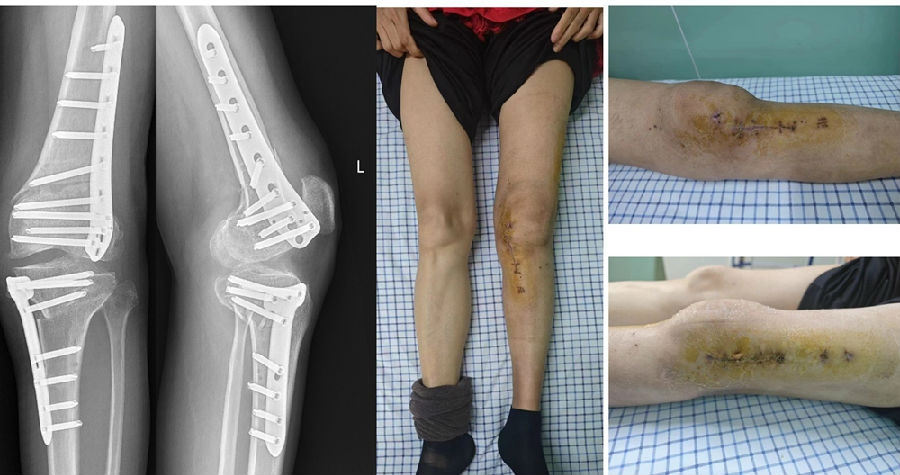

术中

术中透视

术后X线片

术后1个月